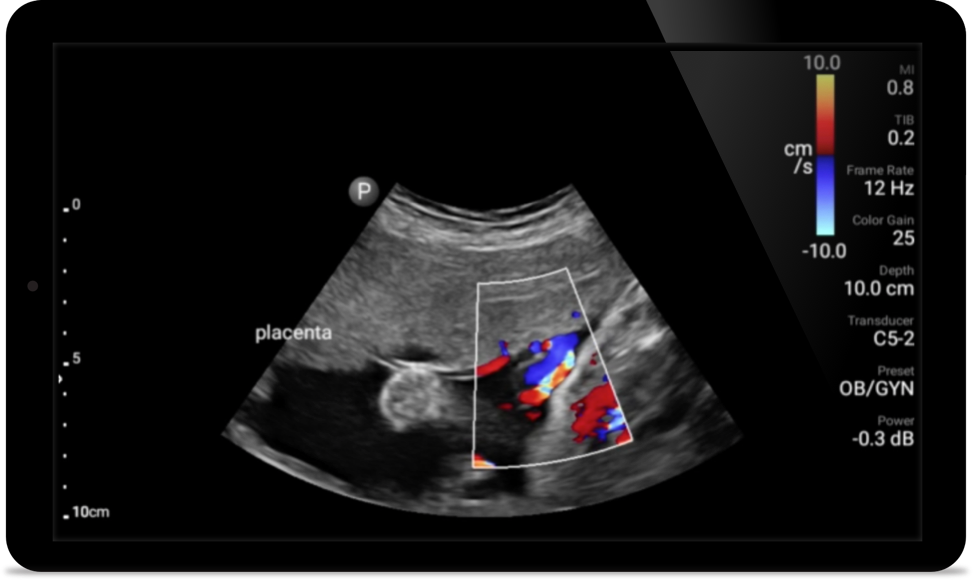

Breng echografie naar het bed

Het gebruik van Lumify aan het bed van uw patiënt kan een waardevol hulpmiddel zijn om de status van de maaginhoud te bepalen en kan hetrisico op pulmonale aspiratie verlagen. Samen kan dit het risico op anesthesiecomplicaties verminderen.